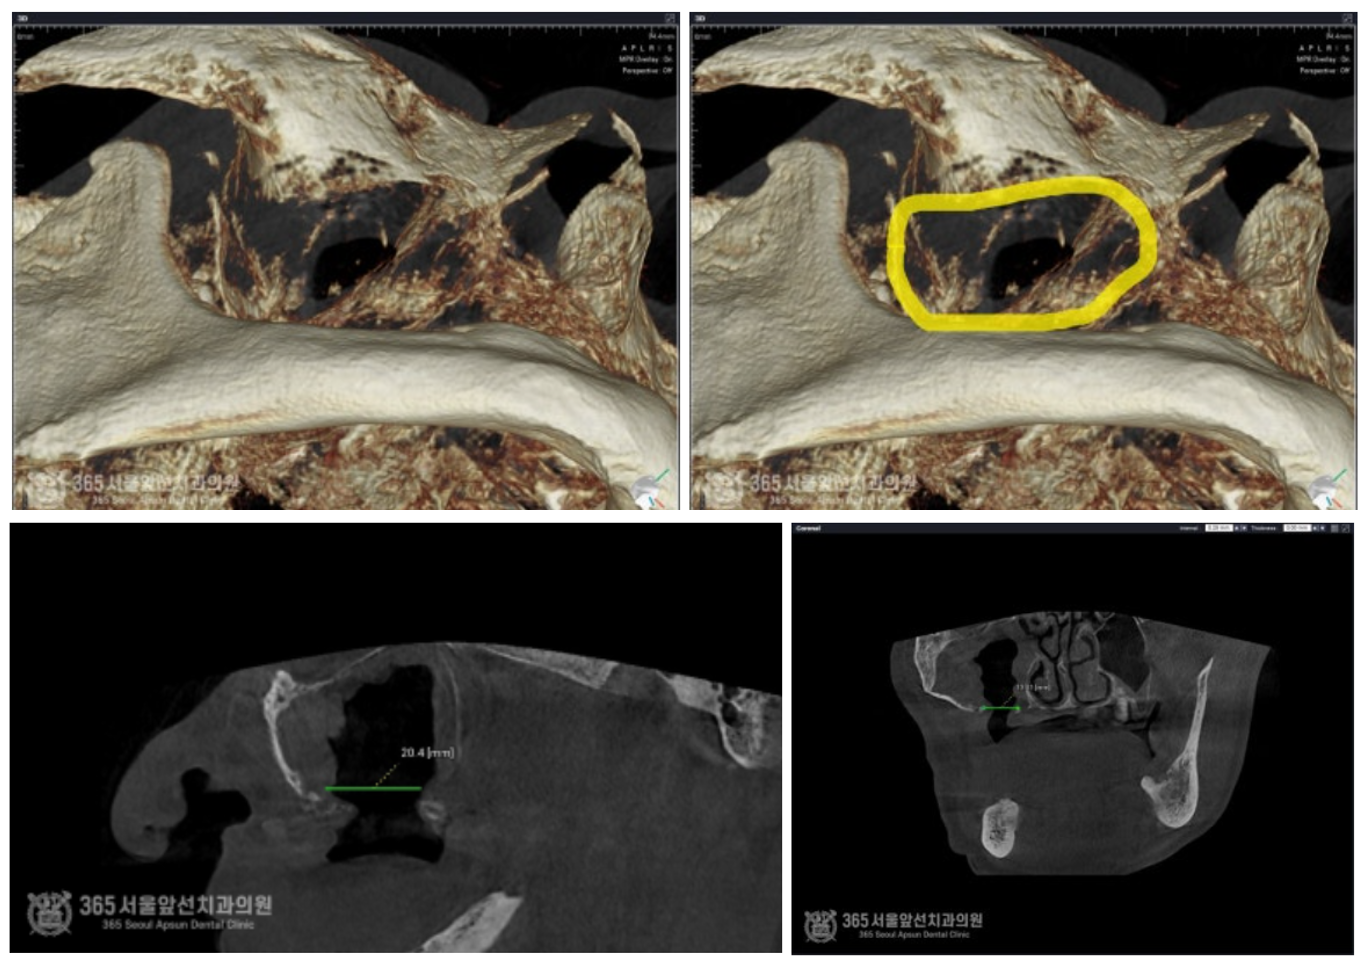

안녕하세요. 석바위시장치과 365서울앞선치과의원입니다. 상기 환자분은 상악동 수술 후 감염으로 인해 상악동측벽 및 상악동하부의 뼈가 모두 녹아서 없어진 환자분이셨습니다. 뼈의 소실로 인해 커다란 구멍(구강상악동누공, Oro-antral fistula)이 발생되어 해당 구멍으로 인해 물을 마시면 코로 물이 넘어간다는 불편감을 호소하고 계셨습니다. 촬영일시 : 2024.07.05 사진상 좌측(구강내 기준 우측)에 커다란 연조직 구멍이 관찰됩니다. 해당 구멍은 입안에서 시작되어 부비동의 일종인 상악동으로 연결되어있습니다. 이를 구강상악동누공이라고 합니다. 구강상악동누공은 발생되면 매우 처치가 어렵습니다. 따라서 구강상악동누공 폐쇄술을 시행해야하며 이는 매우 고난이도 수술에 해당합니다.

촬영일시 : 2024.07.05 CT 상에서 발생된 구강상악동누공의 크기입니다. 매우 커다란 누공이 존재함을 알 수 있습니다. 구강상악동누공 폐쇄술을 시행한 직후 구강내 사진입니다.